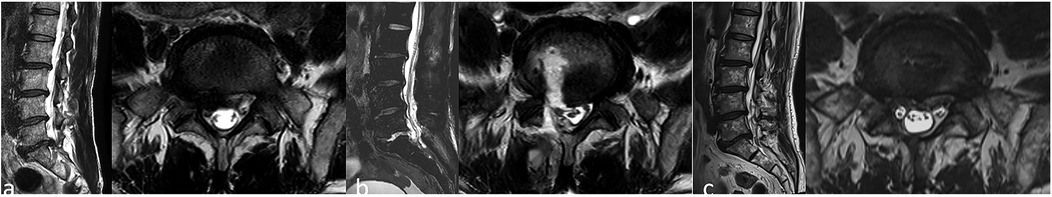

Unilateral Bioportal Endoscopy (UBE), as a minimally invasive technique, has shown significant advantages in the treatment of spinal disorders. However, it comes with surgical risks and complications, particularly acute neurological deficits. In this report, we present a rare case of pneumocephalus as a complication following unilateral dual-channel spinal surgery (UBE) for lumbar disc herniation. A 54-year-old male patient underwent UBE-assisted disc removal surgery for L5-S1 disc herniation. No obvious dural tear was noted during the surgery. Postoperatively, the patient experienced difficulty awakening from anesthesia, with signs of altered consciousness. CT imaging revealed pneumocephalus. On the second postoperative day, cerebrospinal fluid leakage and symptoms of decreased intracranial pressure were observed. After symptomatic treatment, no significant neurological sequelae were noted, and the patient was discharged. Postoperative clinical signs of increased intracranial pressure and imaging evidence of pneumocephalus suggest the occurrence of dural injury.